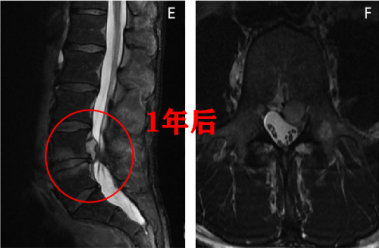

图三:LDH 患者 MRI 显示重吸收的时间为出现症状后 4 个月,图源:DOI: 10.1016/j.neuchi.2018.12.001